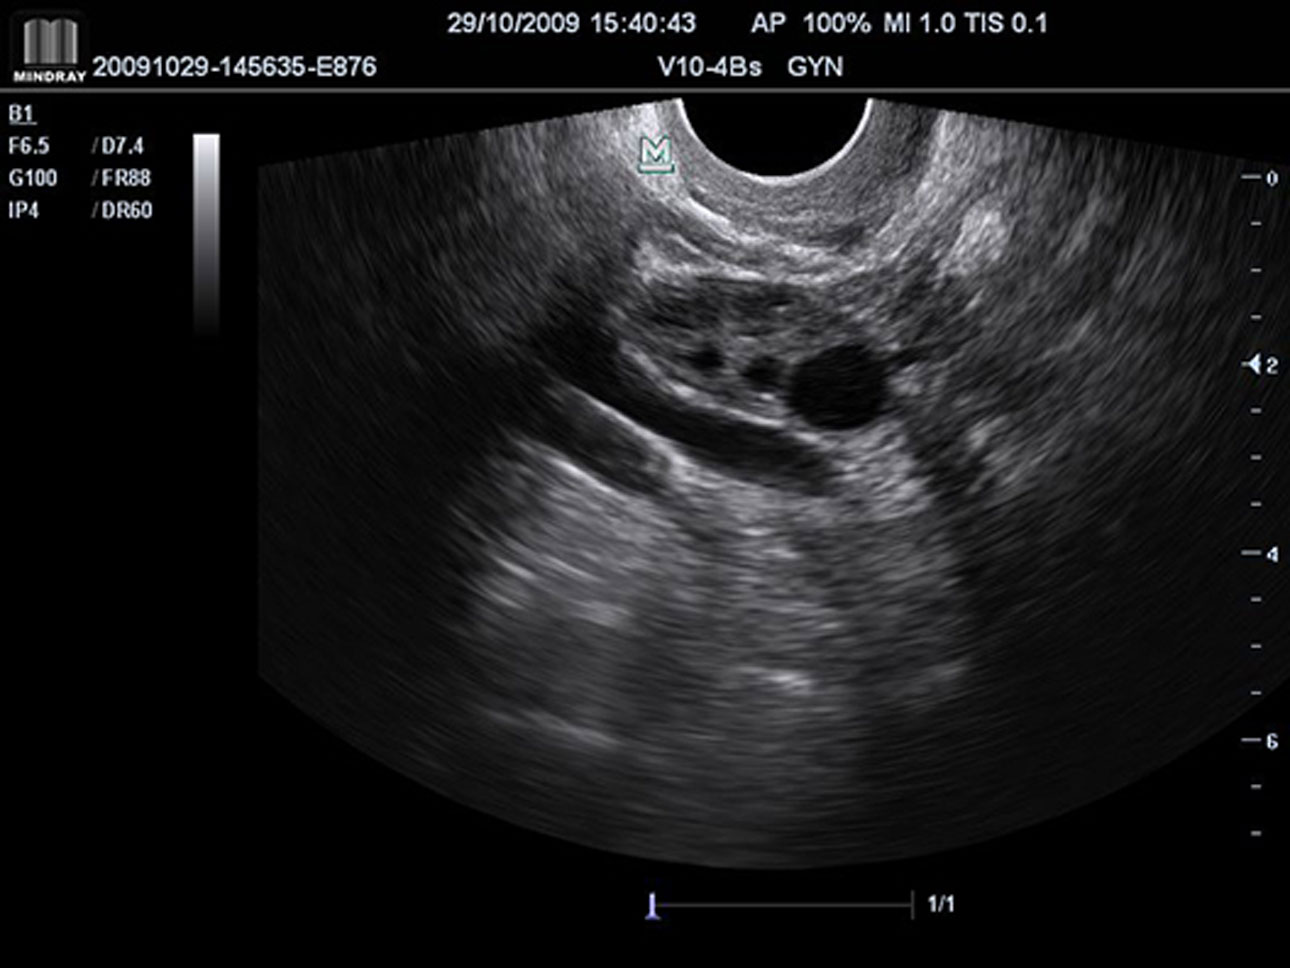

iScapeTM (Real-time Panoramic Imaging)

Get a complete and extended view of the anatomical structure through panoramic imaging, coupled with velocity indication and forward/backward scan ability making scanning much easier, smoother and more controllable.